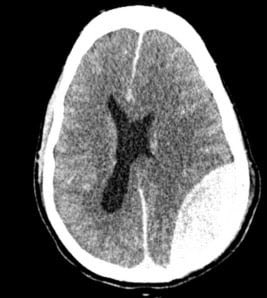

🚑 استكمال موضوعنا السابق عن العلاج المتقدم 💉💉🚑 لزيادة الضغط داخل 💀الجمجمة 💀

🚨 في حالات زيادة الضغط بشكل عالي جدا وظهور علامات Cushing ( تذكر مو لازم كل ٣ علامات)

🚨 راح نتحكم بمعدل ثاني اكيد الكربون CO2 . السبب ان نزول ثاني اكسيد الكربون راح يؤدي الى تقلص الاوعيه الدمويه vasoconstriction وبالتالي يقلل كمية النزيف .

🚨بمعنى اذا قل CO2 بنسبة 1% راح يقل CBF دوران الدم داخل الدماغ 3% .

⚠️لذا السيطره على مجرى الهواء في مثل هالحالات ضروريه عشان ماترتفع نسبة CO2 ثاني اكيد الكربون لانها راح تتسبب بتوسع لاوردة وزيادة النزيف داخل الجمجمه vasodilation.